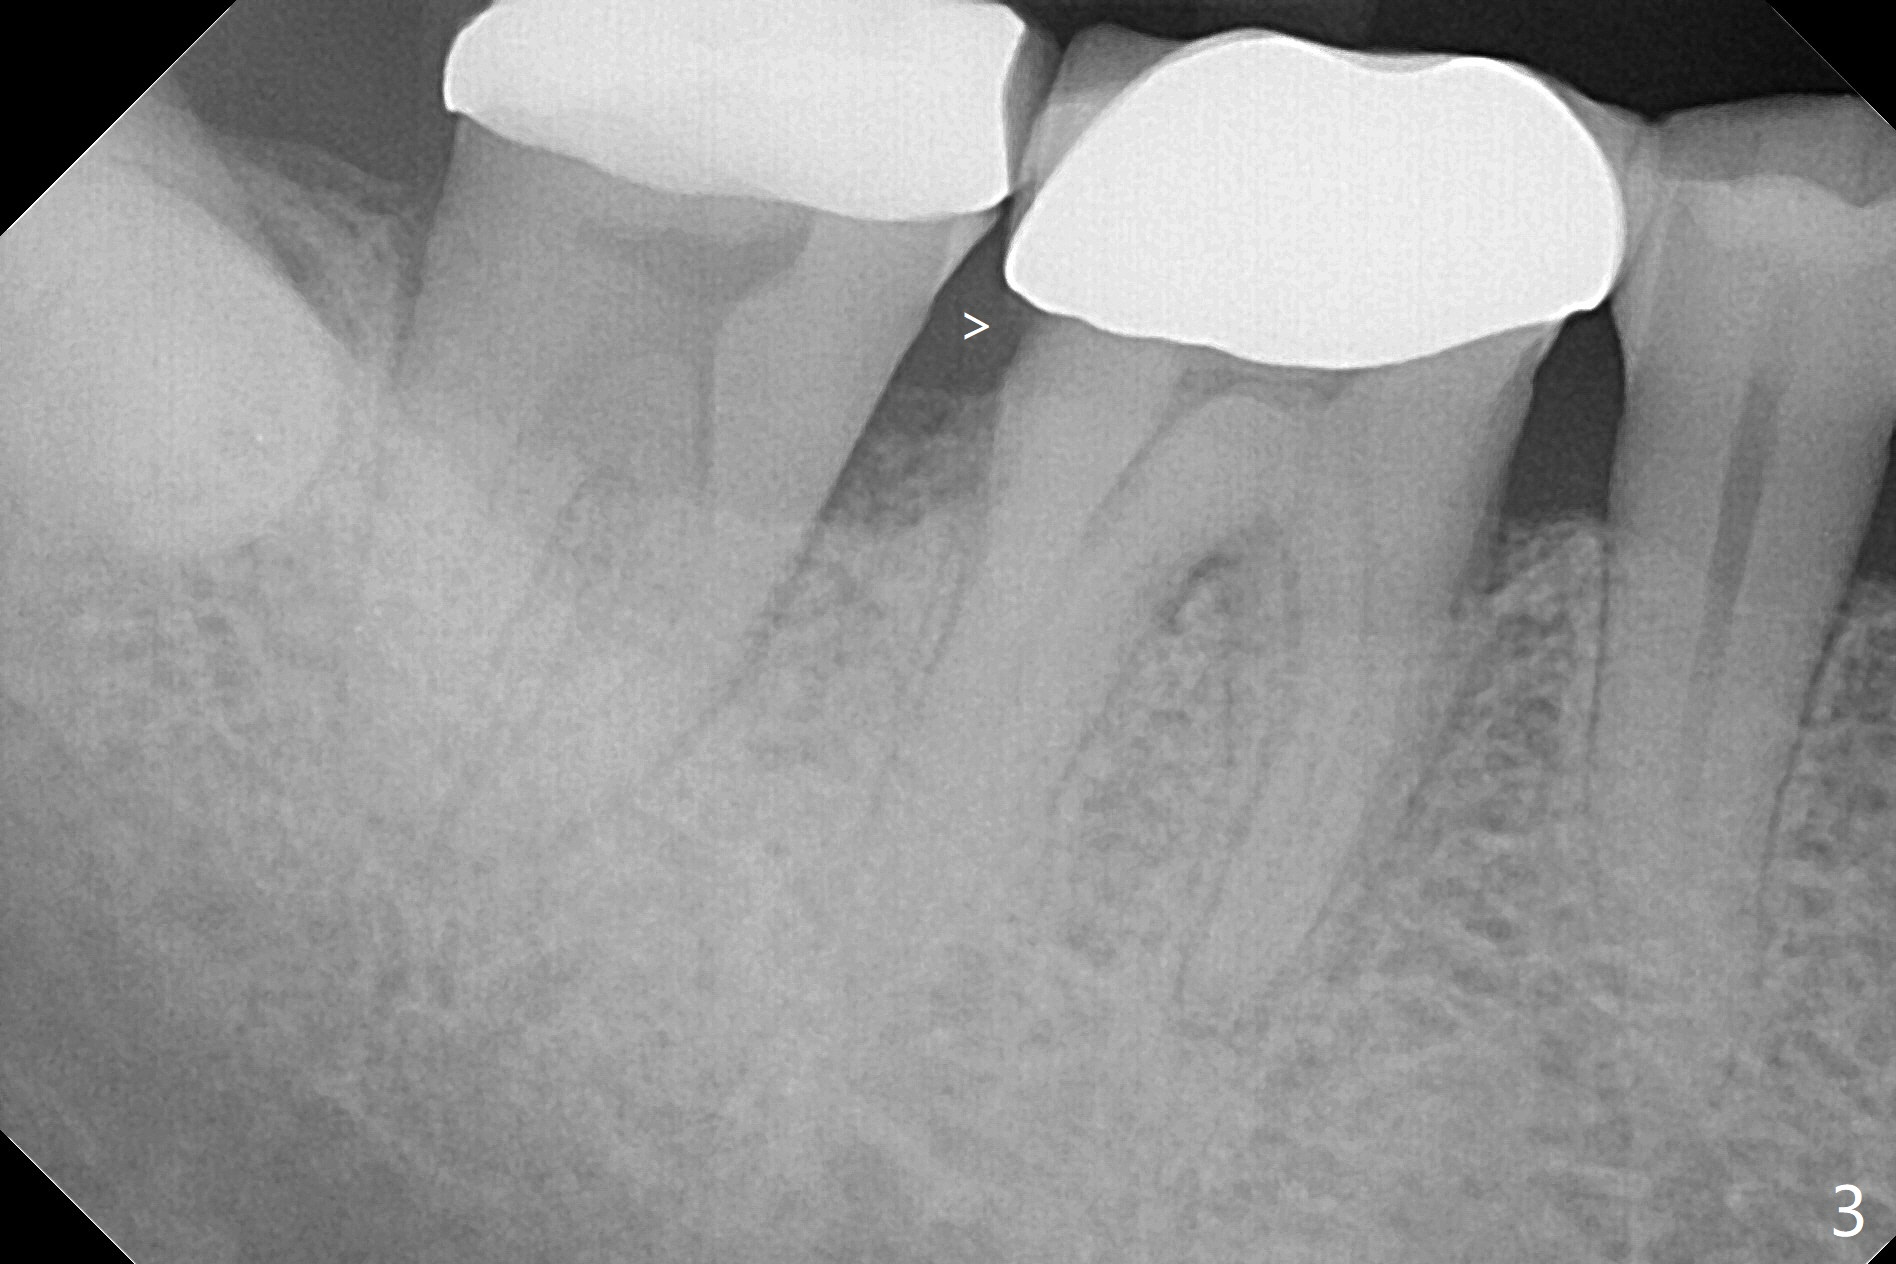

A 53-year-old man returns for #30 crown redo with distal open margin (Fig.1-3 arrowhead) after #4 implant. In addition to the distal margin caries, there is buccal one after removal of the existing crown. Composite build up is done for the buccal cavitation, whereas heavy chamfer margin is prepared distal. BW is taken immediately before cementation with open margin (Fig.4 ^). The latter disappears when the crown is cemented with pressure (Fig.5 arrow).